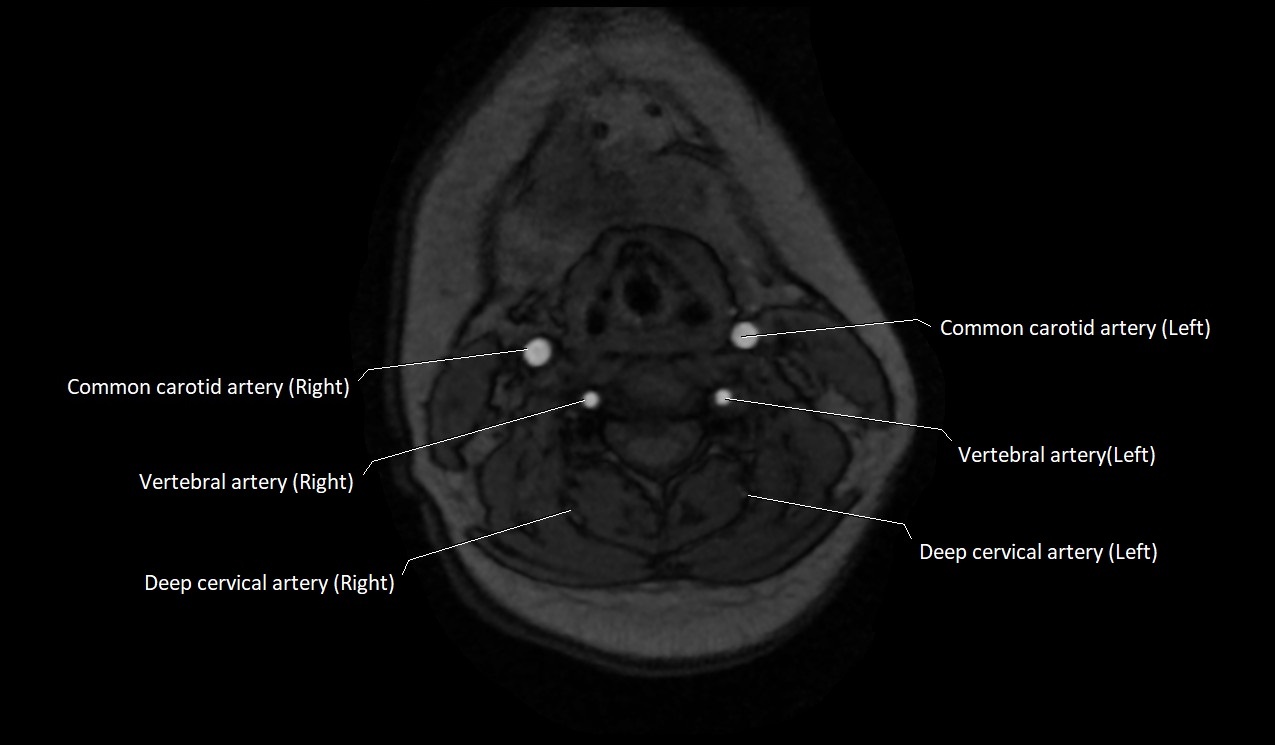

MRI images

image